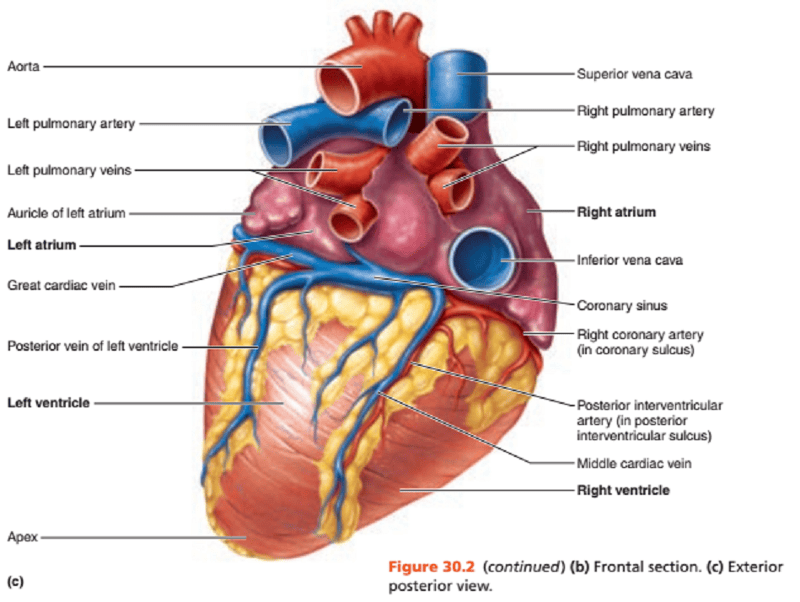

Name the missing parts.

Heart external posterior view

Name the missing parts.

External posterior view

Name the missing parts.

External posterior view